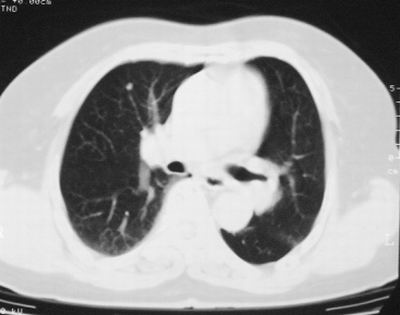

患者,女,64岁,4年前左腮腺"多形性"腺瘤手术治疗史.现复查胸部ct见左下肺块状影,该影与原左腮腺手术是否有联系?

本次复查胸部ct

左下肺癌伴左肺门淋巴结转移

支持考虑左下肺原发性肺癌,并左肺门淋巴结肿大

左下周围型肺癌伴左肺门淋巴结及右肺转移可能性大.

左肺下叶周围型肺癌,支持!(软组织肿块+分叶+毛刺+空泡+胸膜凹陷征)

左下肺软组织密度影,可见分叶,边缘可见毛刺征,胸膜增厚,强烈要求左下肺周围型肺癌